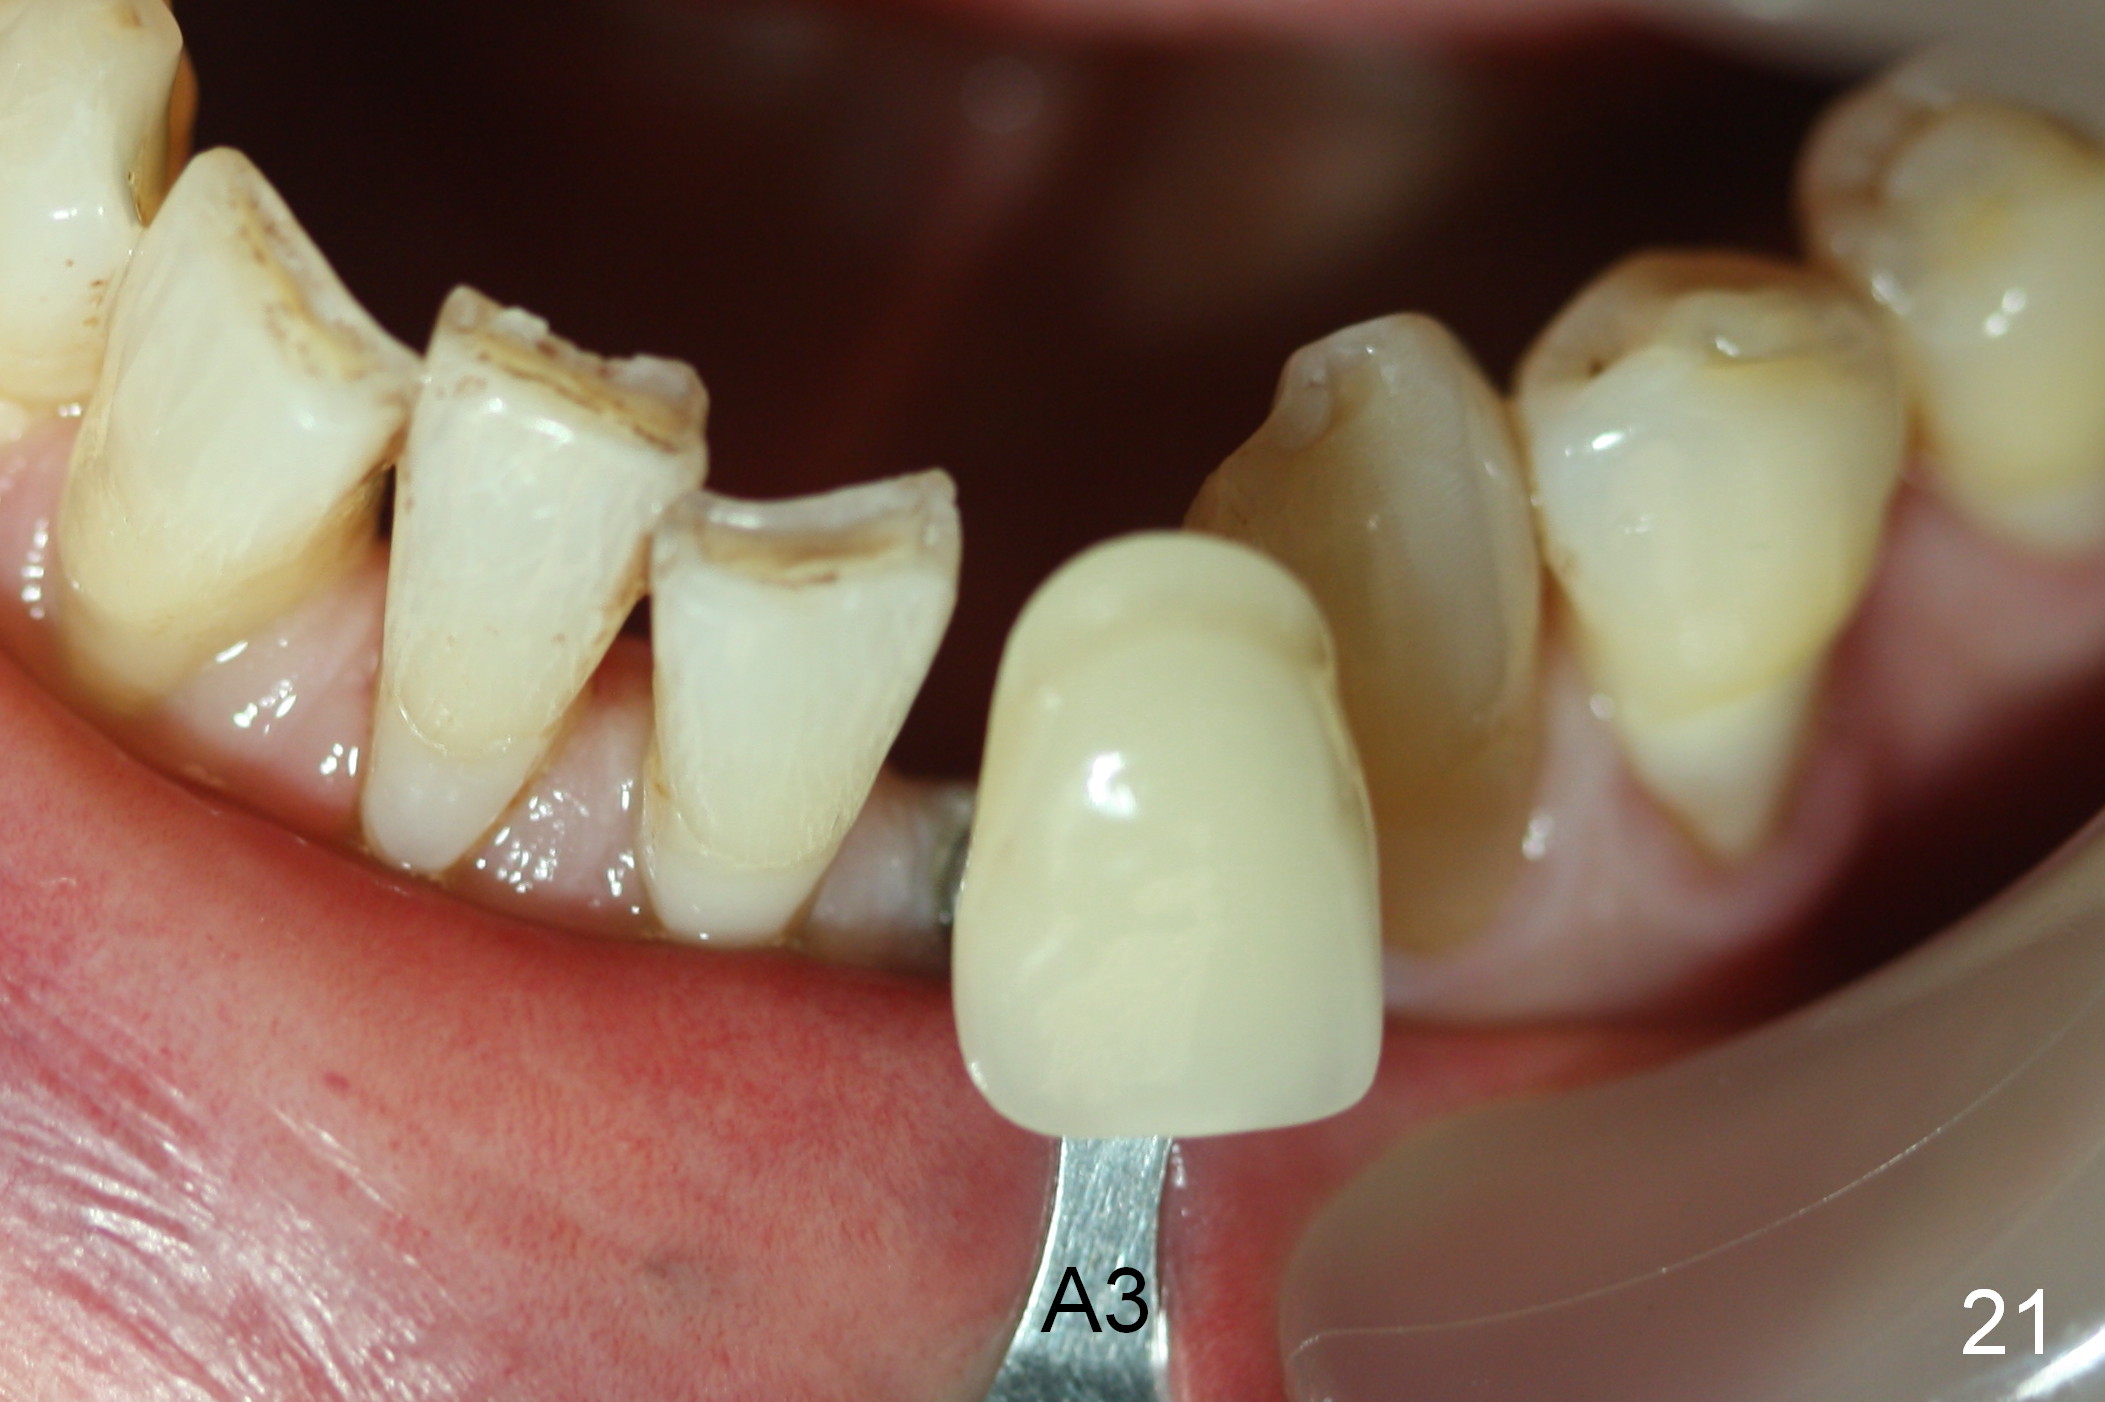

A 74-year-old man has several missing teeth (Fig.1). His 1st goal is to replace the lower left lateral incisor (Fig.2). The residual root has an apical lesion (Fig.3 *). To describe intraop findings, a CT image of a different patient is used (Fig.4 coronal section; B: buccal; L: lingual). After extraction, the buccal plate is found to be thin and low (Fig.5 arrowheads). A 1.5 mm pilot drill (Fig.6 red line) is used to initiate osteotomy in the lingual plate of the socket. Once the drill penetrates the lingual plate, the trajectory changes and the depth is 17 mm from the gingival margin (Fig.7). A PA is taken (Fig.8); it appears that the osteotomy can be extended more apically. When the pilot drill extends to 20 mm, there is sudden empty feeling. The lingual plate has perforated (Fig.9). A new osteotomy is established buccally (Fig.10 pink). To avoid buccal plate perforation, especially in the buccal undercut area (>), the coronal end of the drill has to be tilted buccally (<--). An angled abutment (3x20 mm, 15°) is placed (Fig.11,12). The abutment is modified (Fig.13,14) to accommodate an immediate provisional (Fig.15,16 P). Perio dressing is to be applied to prevent the bone graft from getting dislodged buccally (Fig.15). The dressing is in place 7 days postop (Fig.17).